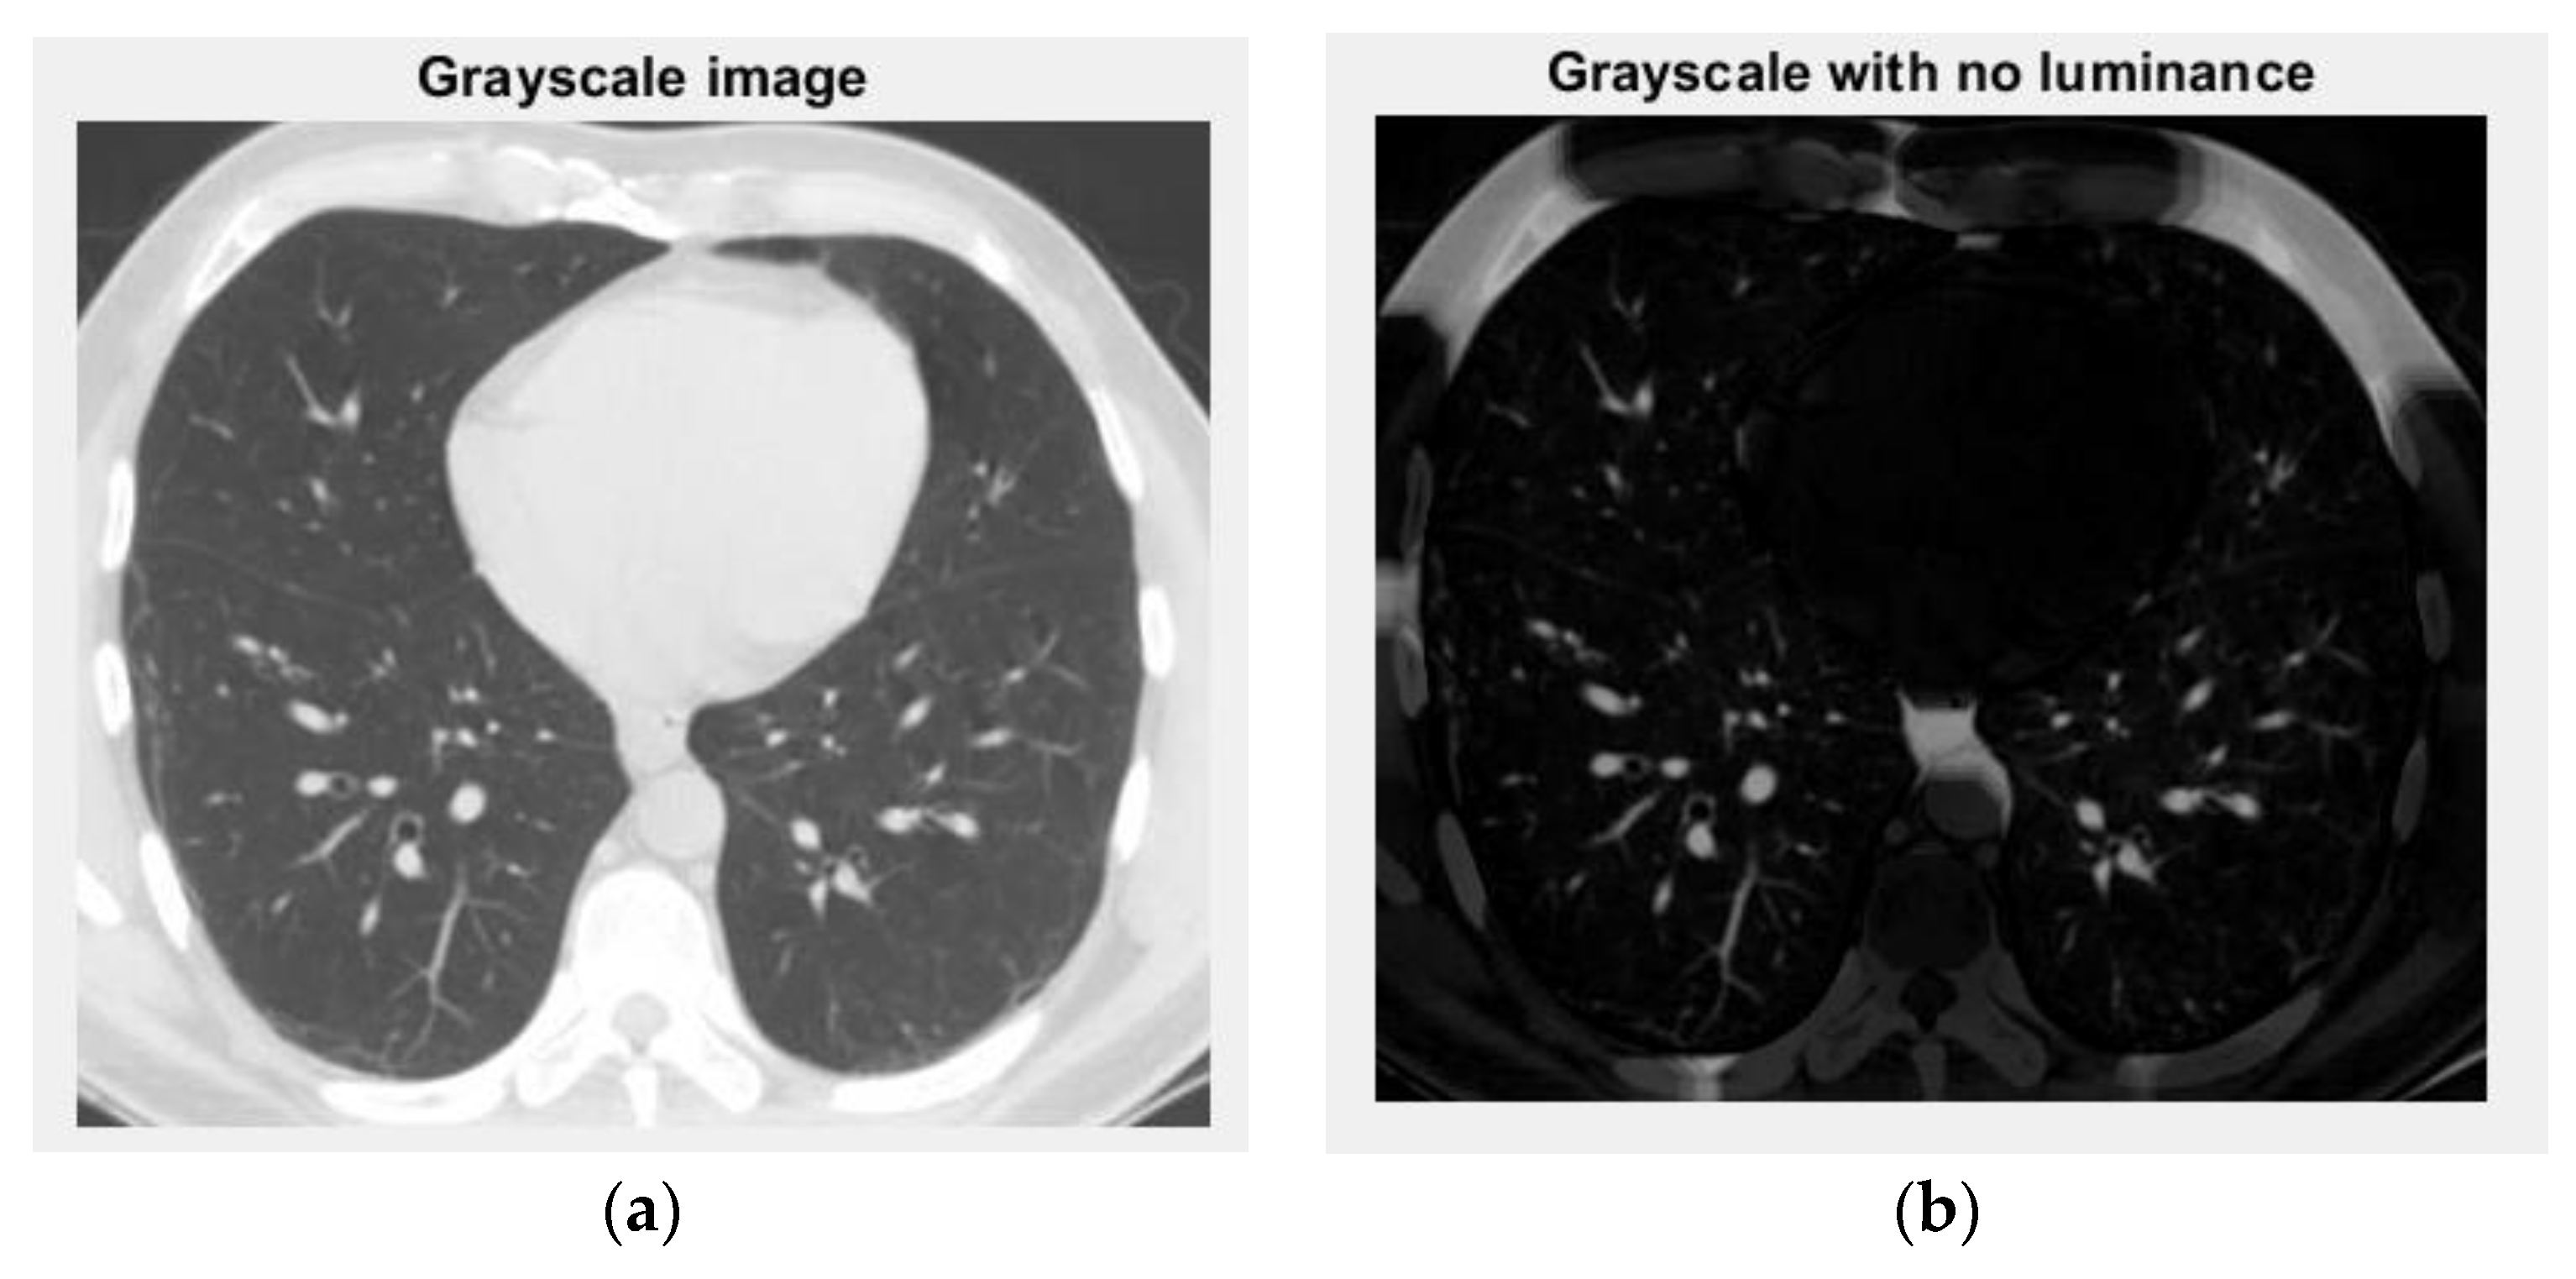

The voxels are usually utilized in scientific research to precisely and quickly focus on volumetric data [24,25]. In a voxels-founded structure morphology, condensation differences in the lung texture can be confronted utilizing the voxels, as seen in the figure above. Figure 12 and Figure 13 are the grayscale images with and without luminance of the COVID-19 lung CT image, respectively, and the filtered versions of the COVID-19 lung CT image.

Figure 12. Grayscale versions of the COVID-19 lung image: (a) grayscale image and (b) grayscale with no luminance.